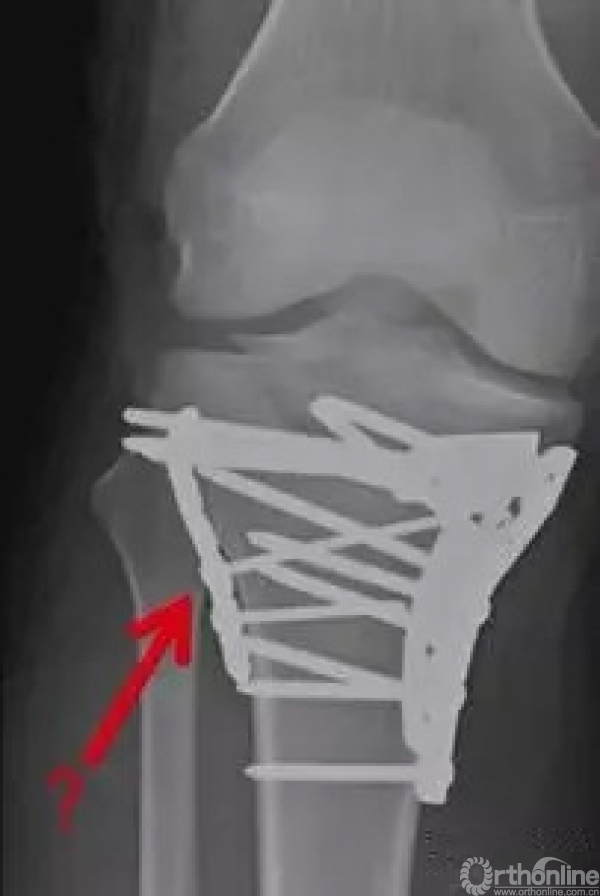

对于这样一个骨折,以下的手术是否合理?

1.外侧钢板是不需要的。

2.内侧的关节面复位严重不足。

这样的错误治疗大家需要记得,外侧的锁定钢板并不能够很好的固定内侧的骨块,达不到butress的作用,想象一下,如果你想要治疗这个骨折,应该把你的手放在哪边进行承托呢?那就是应该置放钢板的位置。